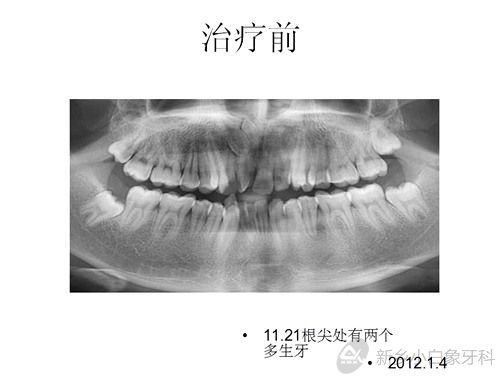

患者赵某某,男,21岁,感觉牙齿不齐,影响美观,于2012年1月4日来我院就诊。经检查,全口恒牙列,磨牙尖牙均中性关系,11牙冠发育畸形且远中扭转,12.22腭侧错位,13.23因间隙不足完全唇侧低位萌出,41.42完全舌侧位,35.45颌面中央有一凸形隆起,牙结石二度,牙龈红肿,探及出血,余未见明显异常。

问题清单:安氏一类错合;11发育畸形;35.45畸形中央尖;牙列拥挤;牙龈炎;11.21根尖处有两个多生牙。

治疗计划:全口固定矫治术;拔除14.24.35.45;排齐与整平牙弓;关闭拔牙间隙;调整咬合关系;11.21根尖处多生牙择期拔除;全口洁治。